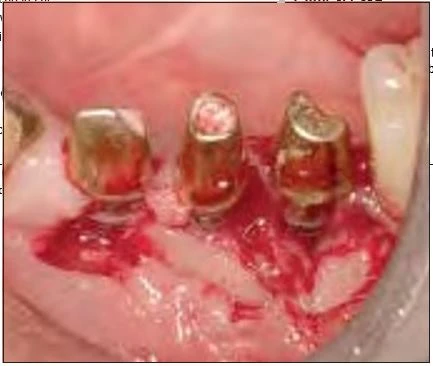

Hình 7: Sau khi lật vạt phía má, một lượng lớn mô hạt viêm được lấy ra bởi tia laser Er:YAG

Hình 8a và 8b: Chìa khóa để lấy đi được mô hạt nhiễm khuẩn bằng laser Er:YAG là không chiếu laser vào chính khối mô hạt mà phải chiếu laser vào nơi giao nhạu giữa mô hạt và mô xương lành. Bằng cách này, mô hạt nhiễm khuẩn có thể được lấy đi trọn một khối duy nhất. Sau khi loại bỏ mô hạt, bề mặt nhiễm khuẩn TiUnite được lấy đi và được tiệt khuẩn.

Hình 9: Sử dụng tia laser Er:YAG kèm theo phun nước giúp implant tránh khỏi sự nóng lên quá mức. Những vụ nổ vi thể được tạo ra khi laser tác động vào nước, chúng giúp loại bỏ máu và những vật cản thấy được

Vào tháng chín 2006, một phụ nữ 81 tuổi được cấy tổng cộng chín implants, năm trong số chúng được thể hiện trong hình 6: vị trí răng nanh trái hàm dưới, răng cối nhỏ thứ nhất và thứ hai, răng cối lớn thứ nhất và thứ hai. Sau 4 tháng, phục hình tạm được thực hiện, và sau 6 tháng bệnh nhân được mang phục hình chính thức. Sau 1 năm, bệnh nhân than phiền về tình trạng sưng tấy quanh implant. Kiểm tra X quang cho thấy tình trạng tiêu xương đáng kể quanh implants ở vùng phần tư phía sau hàm dưới bên trái (Hình 6). Khi cấu trúc trên cùng bị loại bỏ, người ta phát hiên ra rằng implants không hề bị lỏng. Tuy nhiên, tình trạng viêm đã lan sang viêm-đây là một trường hợp rõ ràng của viêm quanh implant tiến triển. Những kiểm tra khác xác định rằng đây là một ca CIST (liệu pháp hỗ trợ ngăn chặn tích tụ – cumulative interceptive supportive therapy) loại D ( độ sâu túi > 5mm, có chảy máu khi thăm khám, và tiêu xương > 2mm). Sau khi tiêm thuốc tê tại chỗ (2% xylocaine), vạt phía má được lật lên ở vị trí phần tư hàm dưới trái. Tuy implants không bị lỏng, nhưng lại thấy tình trạng tiêu xương đáng kể và sự hình thành mô hạt (Hình 7). Mô hạt nhiễm khuẩn được cắt bỏ và lấy đi bằng tia laser với đầu PS600T ở năng lượng 50mJ và 20 PPS kèm với phun nước tiệt trùng ở lưu lượng 5mL/min (Hình 8a và 8b). Mô hạt thường được loại bỏ bằng nạo, nhưng máu chảy ra do nạo làm vùng điều trị không được nhìn rõ ràng. Sử dụng tia laser Er:YAG cùng phun nước để loại bỏ vấn đề này. Việc áp dụng phun nước và những sự nổ vi thể (xảy ra khi tia laser bắn vào nước) sẽ giúp giữ cho vùng làm việc luôn được nhìn thấy rõ ràng.

Sau khi lấy đi mô hạt nhiễm khuẩn, bề mặt implant nhiễm khuẩn được tiệt trùng bằng cách lấy đi lớp bề mặt TiUnite. Một đầu PS600T được hướng dẫn di chuyển nhẹ trên bề mặt ở năng lượng 50 mJ và 20 PPS với lưu lượng phun nước là 5mL/phút. Lớp nhiễm khuẩn được lấy đi nhờ các bọt nổ vi thể gây ra bởi phản ứng của tia laser Er:YAG với nước.

Vùng xám hơi tối có thể được thấy trên bề mặt đã được cắt bỏ lớp nhiễm khuẩn, đây không phải là kết quả của quá trình carbon hóa và đó là bề mặt của titan mới. Implants thường được đặt chiều thẳng đứng, và khi tia laser chiếu vuông góc với implant, chúng có thể chạm tới từng chi tiết của các ren và tiệt trùng triệt để lớp titan oxit nhiễm khuẩn bằng cách lấy đi từng lớp một. Một mảnh xương ghép tự thân được cấy vào và che lại bằng màng tự tiêu, sau đó vị trí này được đóng lại theo cách thông thường.